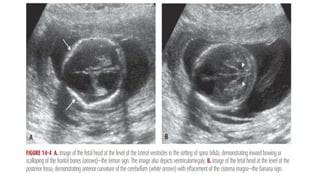

• #9 Targeted Sonography More than 25 years ago, Nicolaides and colleagues (1986) described frontal bone scalloping—the lemon sign, and anterior curvature of the cerebellum with effacement of the cisterna magna—the banana sign—in second-trimester fetuses with open spina bifida These investigators also frequently noted a small biparietal diameter and ventriculomegaly in such casesthe size and location of spinal defects (Chap. 10, p. 202). Using these findings, experienced investigators have described nearly 100-percent detection of open NTDs (Norem, 2005; Sepulveda, 1995). Overall NTD risk may be reduced by at least 95 percent when no spine or cranial abnormality is observed Most centers use targeted sonography as the primary method of evaluating maternal serum AFP level elevation. The American College of Obstetricians and Gynecologists (2013b) recommends that women be counseled regarding the risks and benefits of targeted sonography and amniocentesis, the risk associated with the degree of AFP level elevation or other risk factors, and the quality and findings of the sonographic examination before making a decision. Watson and coworkers (1991) reported that 99 percent of fetuses with open spina bifida had one or more of these findings. In addition to these cranial findings, transverse and sagittal images of the spine are increasingly used to characterize